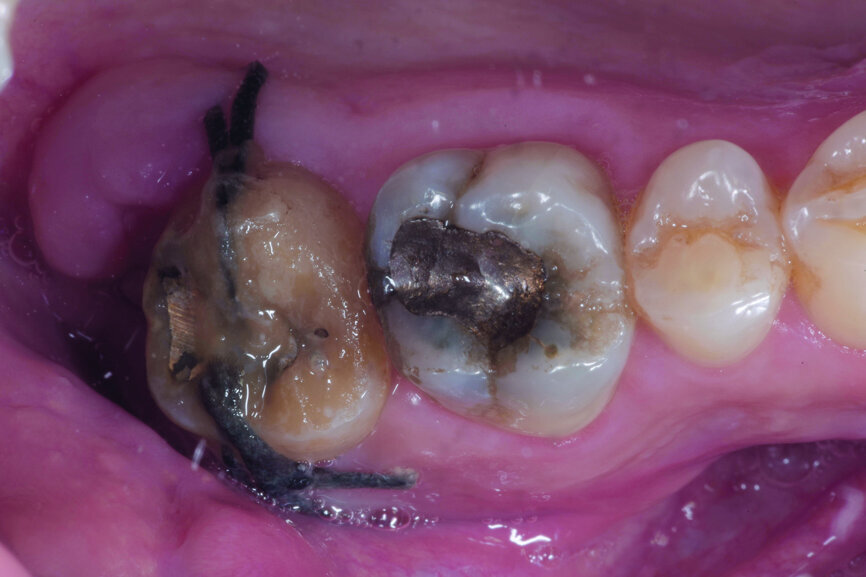

Fig. 1: Pre-op occlusal view.

A 47-year-old male patient in a good medical condition and a non-smoker was referred to our dental practice for endodontic retreatment of the right maxillary second molar. The dental history revealed that the tooth had been endodontically treated three months before because of acute pulpitis. After the treatment, the patient complained of pain on chewing. Antibiotics and a non-steroidal anti-inflammatory drug were prescribed, but the pain remained. After a month, a sinus tract appeared. The tooth was retreated in another practice without success. The clinical inspection revealed the presence of a sinus tract near the apical region of tooth #17. The tooth had been prepared for a full crown, but was without even a temporary crown, and the access cavity had been closed with temporary filling material. Cracks were evident on the buccal and mesial surfaces. Periodontal probing showed a deep pocket (> 12 mm) on the distal aspect of the root trunk (Figs. 1 & 2). The periapical radiograph showed a radiolucency between the roots of the second and third molars. The radiographic appearance of the endodontic treatment was good, without clear evidence of periapical radiolucencies (Fig. 3). A perforation of the pulp chamber floor was suspected. A CBCT scan was performed (Figs. 4–7), and it confirmed the suspicion of perforation, along with the presence of a large periradicular radiolucency and an unfavourable root shape.